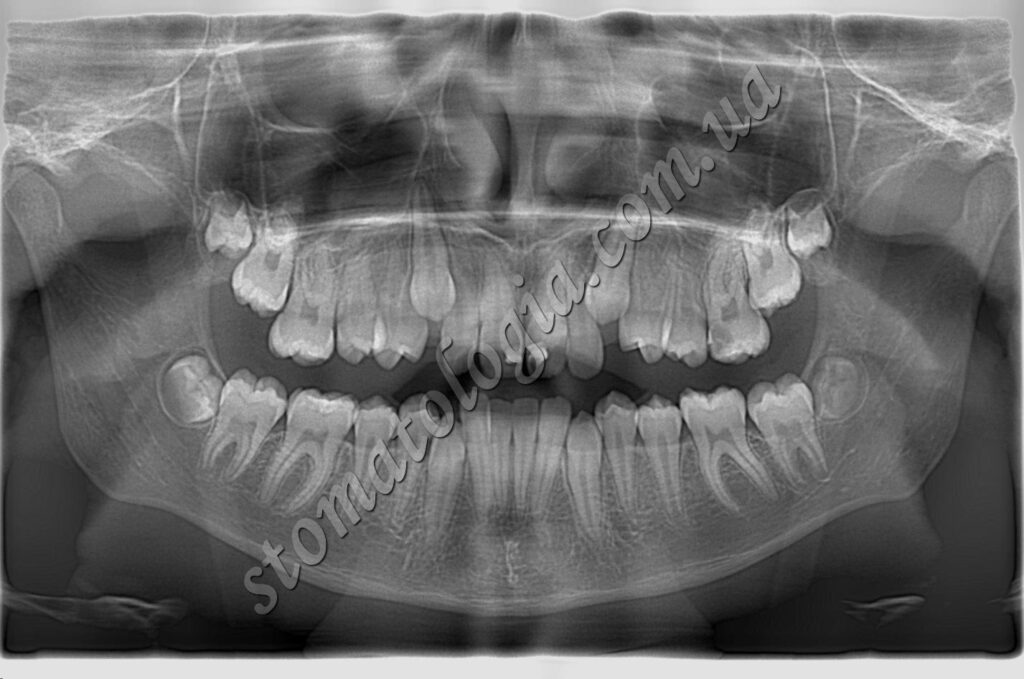

Дистоповані та ретиновані зуби мудрості підлягають видаленню